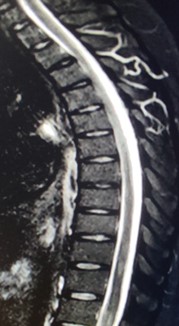

Se solicitó inicialmente Imagen de resonancia magnética (IRM) de columna lumbosacra simple y estudios de neurofisiología. La electromiografía más neuroconducciones de las 4 extremidades reportó neuropatía mielínica de expresión leve del nervio peroneo motor. Imagen de resonancia magnética lumbosacra simple muestra hallazgos compatibles con aracnoiditis adhesiva (figura 1). Ante estos hallazgos, se complementan estudios con resonancia torácica y cerebral con contraste. En la resonancia de columna torácica, se observa incipiente siringomielia (figura 2.) y la resonancia cerebral con contraste no mostró alteraciones.

Figura 2

A nivel T10-T11 se identifica una lesión focal ovoide de contornos claramente definidos, de aproximadamente 10 mm de diámetro mayor, en el plano craneocaudal, de localización central en el cordón medular, hiperintensa en las imágenes. Incipiente siringomielia y alteración en la dinámica del líquido cefalorraquideo.